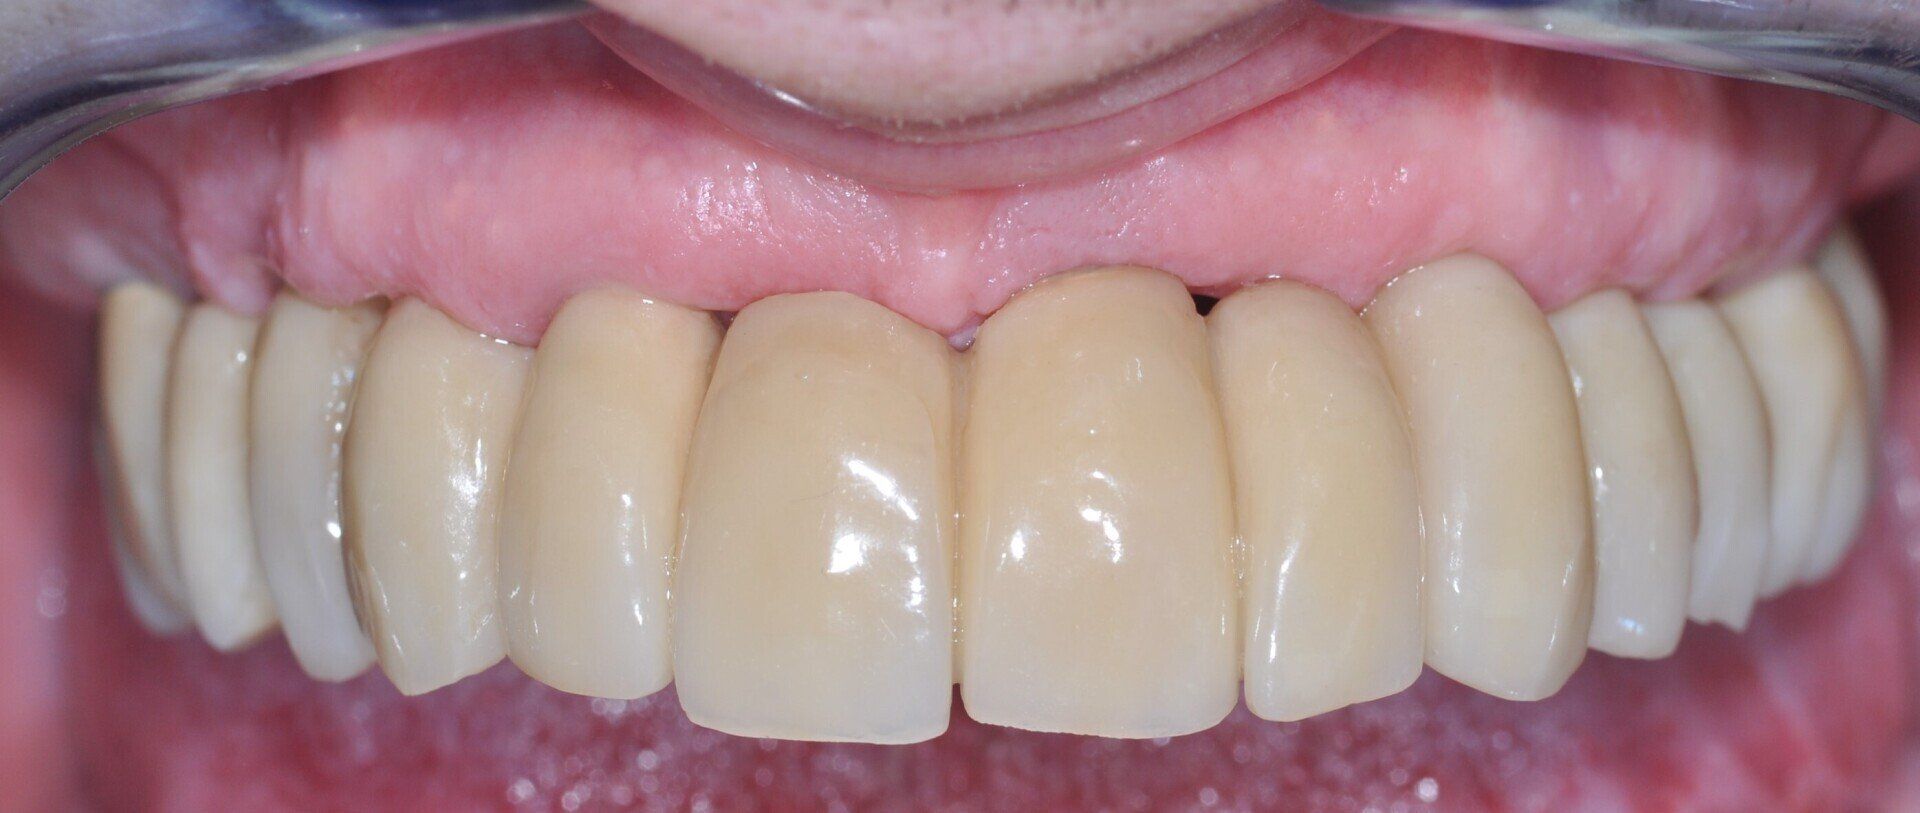

Fig. 5_Foto intra-orale dei tessuti peri-implantari al momento della disconnessione del provvisorio a 4 mesi dalla chirurgia. In foto si apprezza la salute e il buon condizionamento morfologico delle mucose.

Fig. 6_Foto intra-orale a 3 anni dall’intervento in cui si apprezza la salute e il buon mantenimento delle mucose.